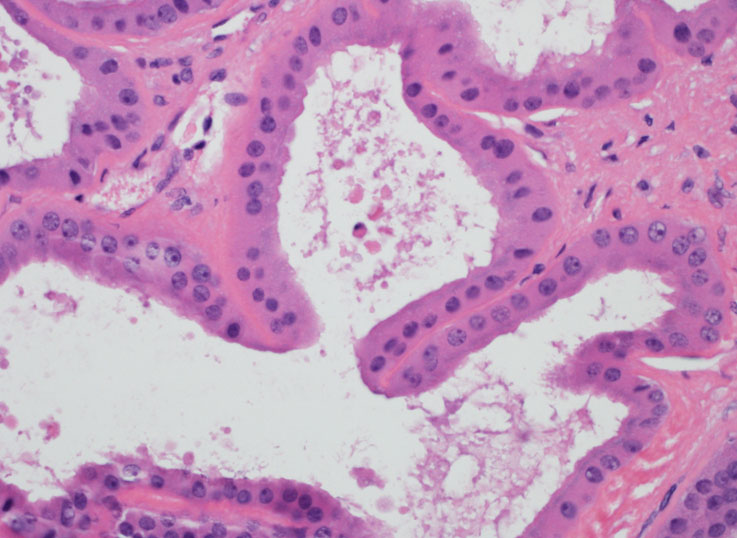

| Pathologist 15 | Tubulocystic RCC | Not typical |

3rd photo is strange for me......part of the tumor? |

| Pathologist 18 | Tubulocystic RCC | Typical |

image 3? |